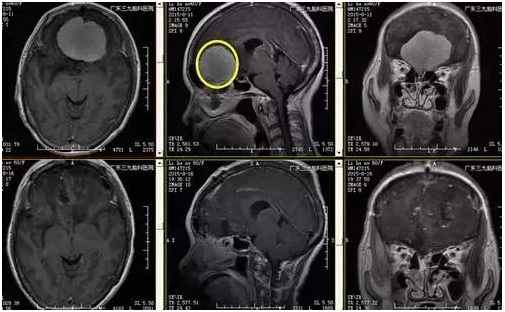

↑手术前后对比

根据病人情况科室行全麻下嗅沟脑膜瘤切除术,手术由神经外一科主任张良主刀,术程顺利,术后病理提示过渡型脑膜瘤(WHO I级),术后经系统康复治疗后,患者病情恢复良好出院。

手术是治疗嗅沟脑膜瘤特别是巨大嗅沟脑膜瘤的唯一有效方法。巨大嗅沟脑膜瘤的切除存在一定难度:(1)术中额部骨瓣需钻孔足够低,暴露颅底;(2)额窦开放需封闭好,防止继发颅内感染;(3)避免反复牵拉脑组织造成术后水肿加重;(4)肿瘤供血丰富,需暴露后处理基底、切断血供(5)后极常累及垂体、视交叉,处理时需减少对垂体柄、大脑前动脉及视交叉的损伤。本例患者肿瘤供血丰富,术前肿周水肿明显,术中出血约200ml,未输血,术后恢复良好,未有明确并发症。